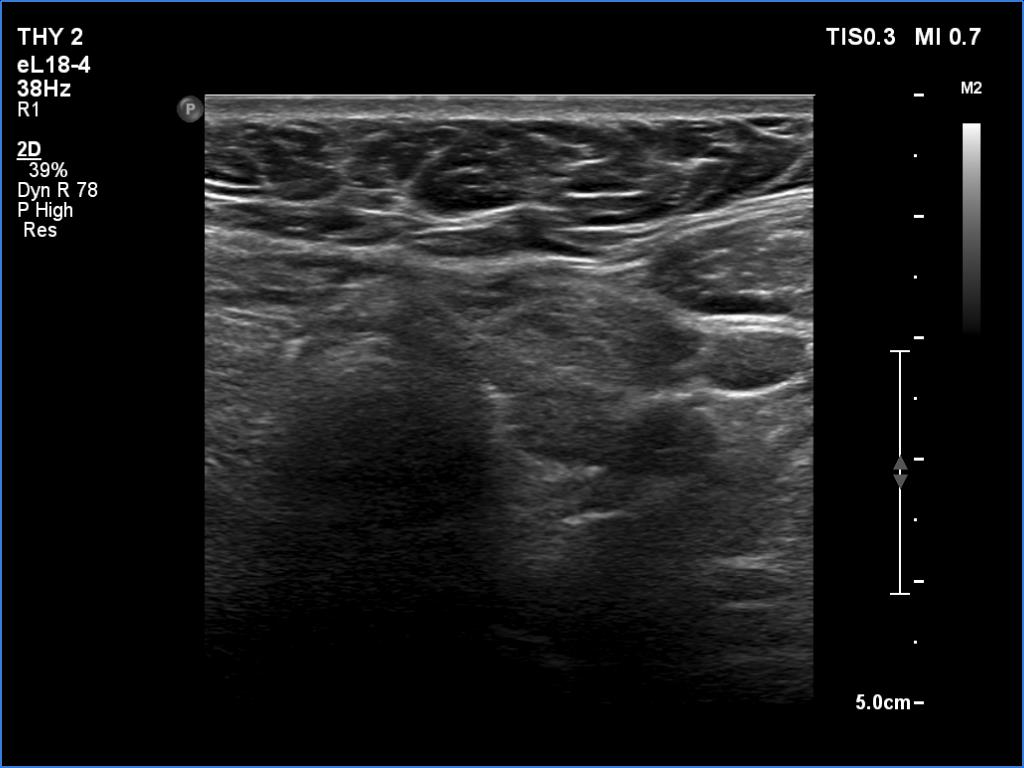

Ultrasonography. The thyroid was echonormal. Using higher frequency three discrete hypoechoic lesions were found, one in the middle dorsal part of the right lobe, one in the middle and a third one in the lower dorsal part of the left lobe. By decreasing the frequency, the presence of only the third one could be confirmed.

Comment. It is a rule that larger the distance from the probe worse the permeability of ultrasound wave. This can lead in certain patients (overweighted ones or frequently in men) that the dorsal part of the thyroid lobe can deceptively look darker, i.e. hypoechoic. If we have any doubt, by lowering the frequency i.e. increasing the penetrance, the real situation can be much better to judge.

This happened in this patient. If we would trust the pattern gained by higher frequency settings, we would falsely diagnose at least one additional nodule.